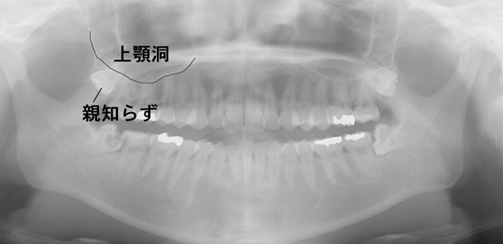

パノラマレントゲン撮影で得られる画像は2次元のため、下顎神経の走行や上顎洞と歯の詳細な位置関係を知るのが難しい場合があります。

CT像では歯の生え方や神経の走行、上顎洞との位置関係などを3次元で確認することができるため、より正確な診断が可能です。主治医が総合的に判断しCT撮影を提案された場合はより安全な抜歯のために受けることをお勧めいたします。また患者様のご希望でも撮影は行いますのでお申しつけください。

パノラマX線写真

デンタルX線写真う蝕(虫歯)も大きく、治療困難、抜歯が適応です。